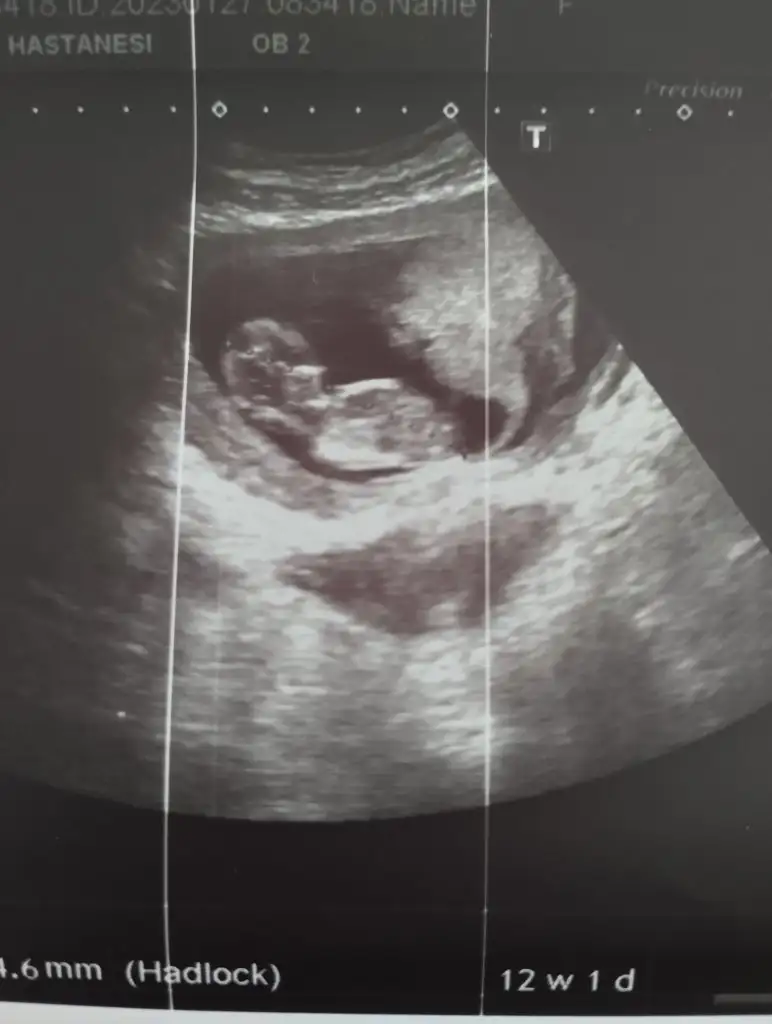

İkisine de erkek diyorum cNim:)Evet karından

Çok teşekkür ederim canım:)) eşim henüz gebelik bile yokken ikiz oğlanlarimiz olur inşallah diye dua ediyorduİkisine de erkek diyorum cNim:)

İnş doğru tahmin etmisimdirÇok teşekkür ederim canım:)) eşim henüz gebelik bile yokken ikiz oğlanlarimiz olur inşallah diye dua ediyorduikiz olduğunu öğrendigimde ilk şoku yaşadım ikisi de erkek olursa ikinci şok olur artık benim gönlümde bir kız bir erkek olsa da öncelikle sağlıklı sıhhatli olurlar inşallah

Ben öyle gordm bakalm belki soldaki kızdir öyle bile olsa Bi kız Bi erkek, 2 erkek ikisi de mis gibi